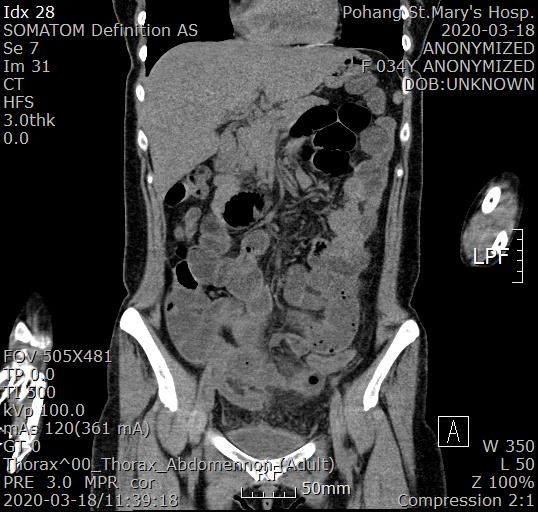

복부 CT 검사를 진행했습니다.

조영제를 사용하지 않고 CT검사를 진행했는데 충수돌기염 천공으로 인한 복막염이 의심되는 상황입니다.

충수돌기염은 흔히 맹장염으로 알고 있는 질환이며 염증이 심한 경우 충수돌기에 구멍이 생기게 되고 이를 천공이라 합니다.

물론 천공이 진행되고 나면 장내 물질이 복강내로 누출되면서 복막염을 유발합니다.